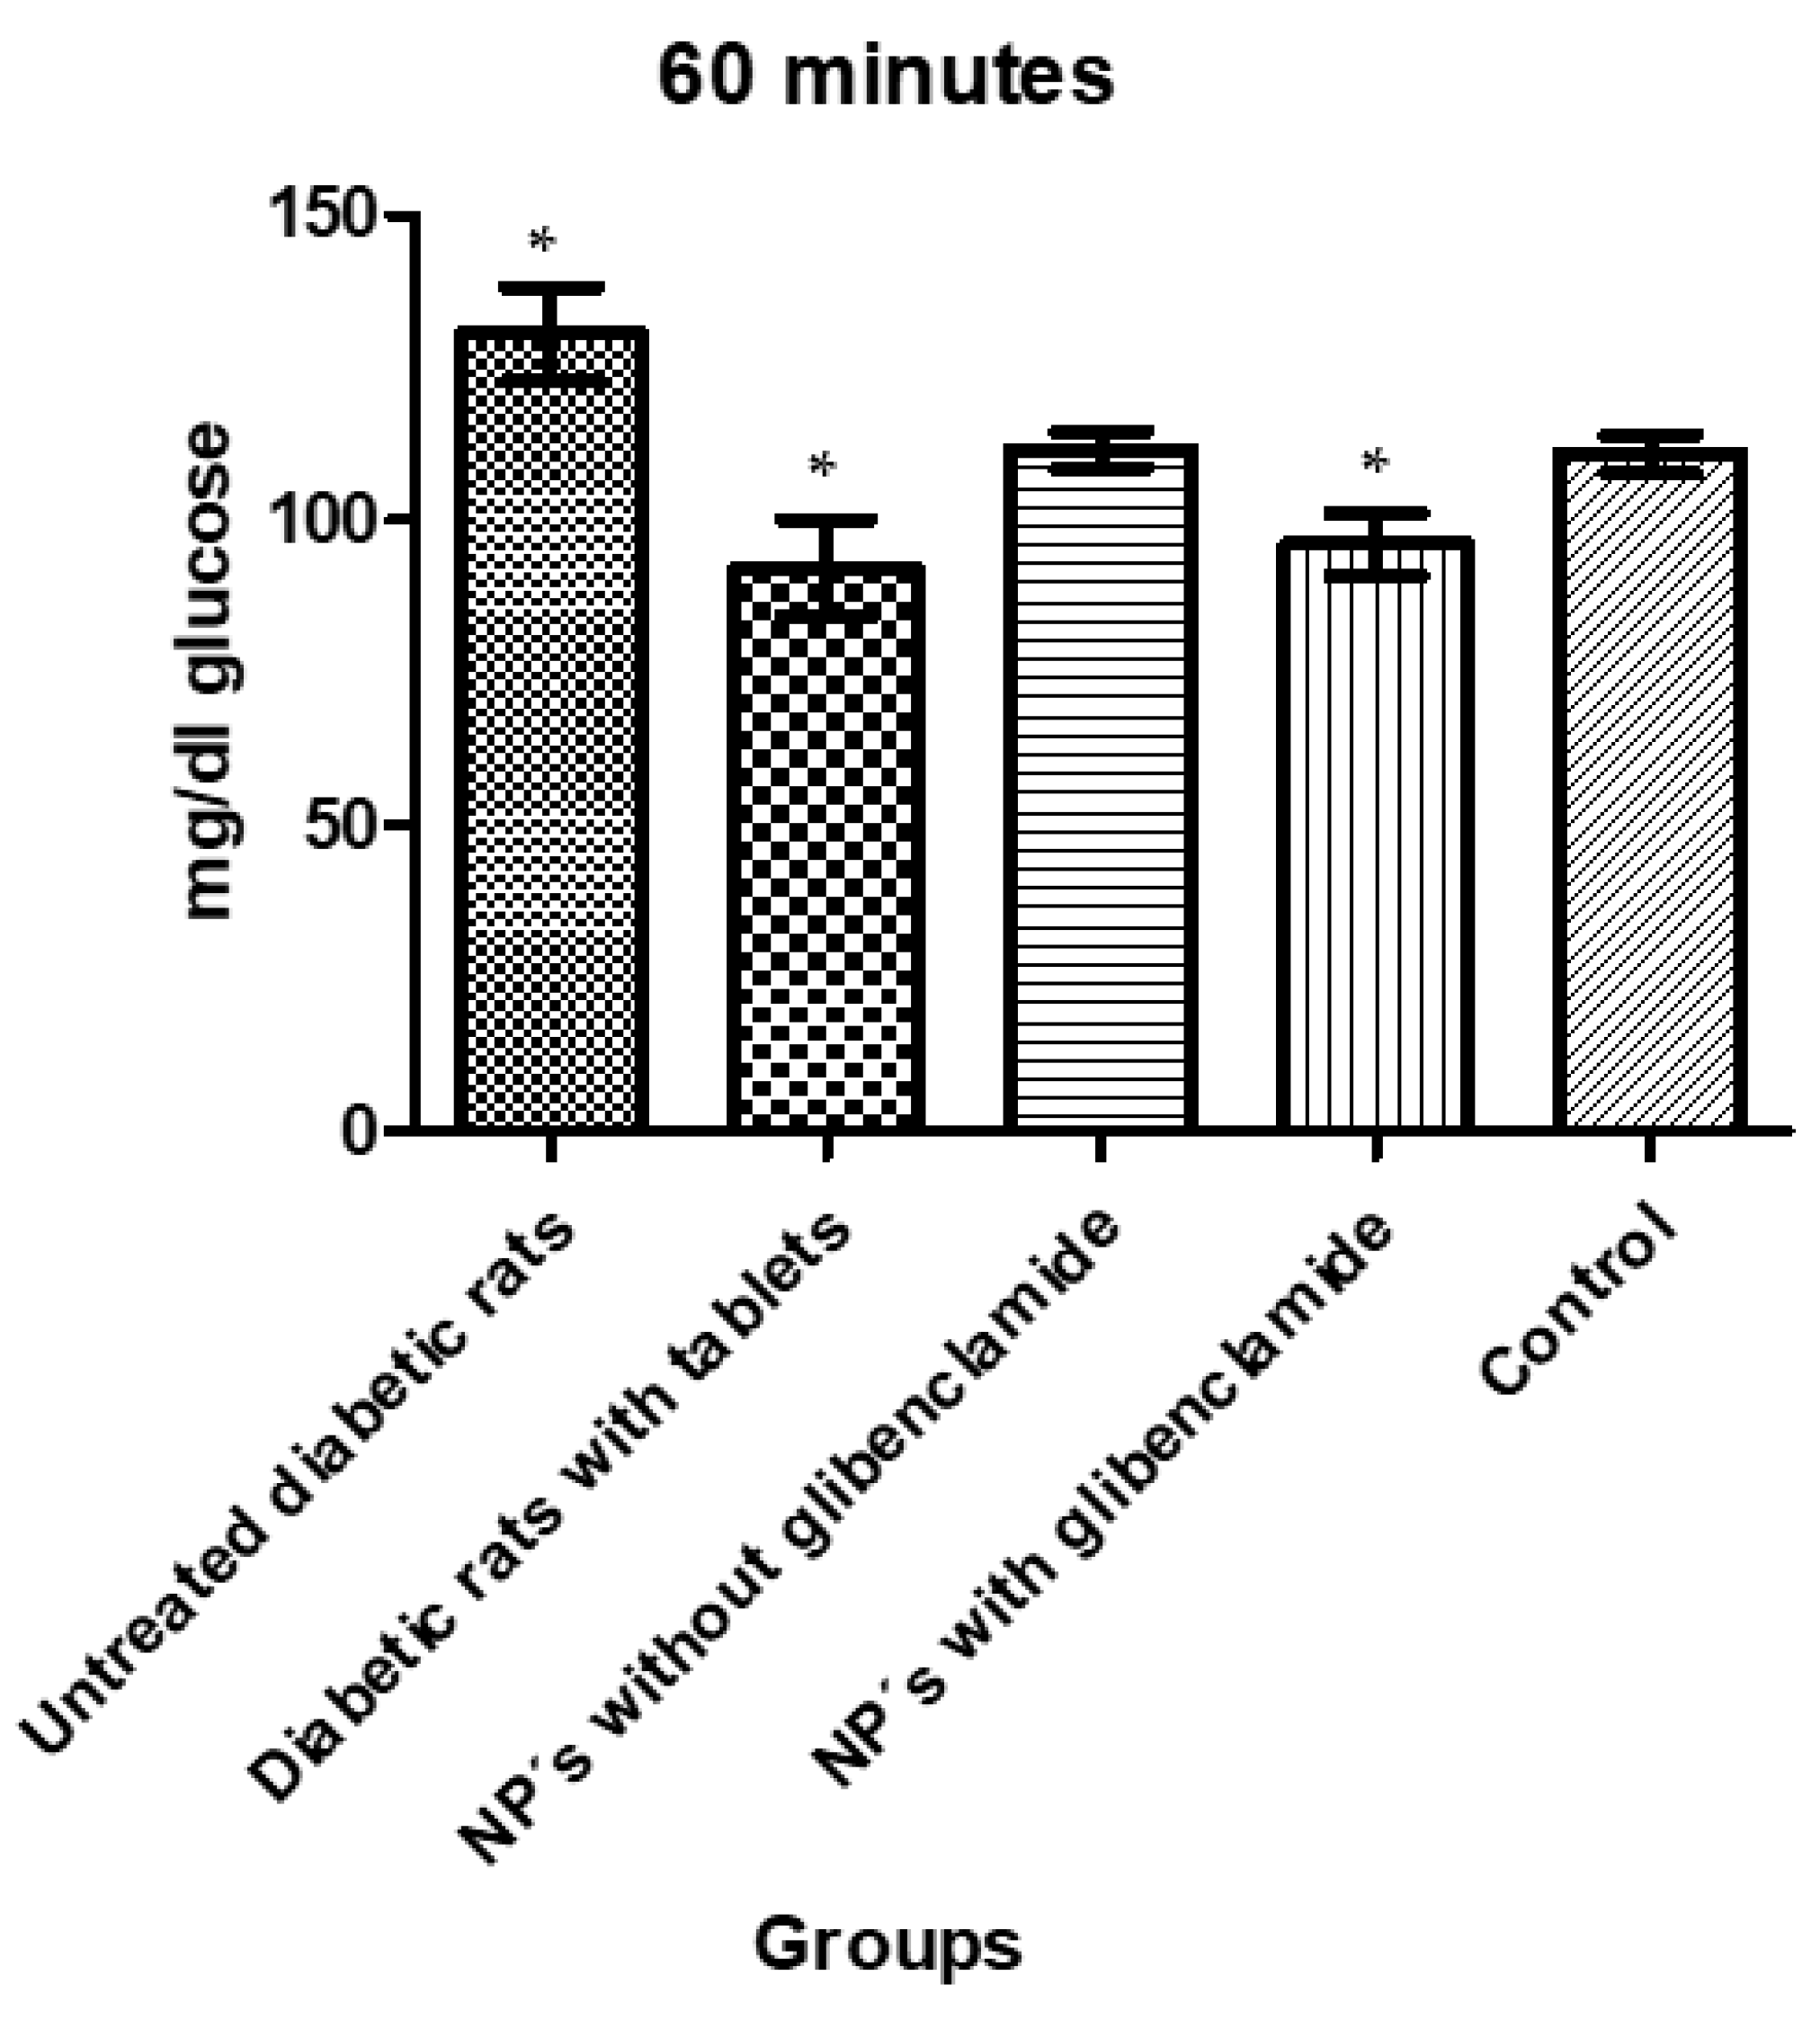

3.1.7. In Vivo Tests

| Animals Were Divided into 5 Different Groups with 5 Individuals Each as Follows: |

|---|

| Group 1: untreated diabetic rats |

| Group 2: diabetic rats with conventional pharmaceutical form (tablets) |

| Group 3: diabetic rats administered with NP without glibenclamide |

| Group 4: diabetic rats administered with NP with glibenclamide |

| Group 5: control |

| Tukey’s Multiple Comparison Test | Significant p < 0.05 | Summary | 95% CI of diff |

|---|---|---|---|

| Group 1 vs. Group 2 | Yes | *** | 15.42 to 61.18 |

| Group 1 vs. Group 3 | No | ns | −4.005 to 41.76 |

| Group 1 vs. Group 4 | Yes | *** | 11.52 to 57.29 |

| Group 1 vs. Group 5 | No | ns | −3.008 to 42.23 |

| Group 2 vs. Group 3 | No | ns | −41.30 to 2.460 |

| Group 2 vs. Group 4 | No | ns | −25.78 to 17.99 |

| Group 2 vs. Group 5 | No | ns | −40.29 to 2.919 |

| Group 3 vs. Group 4 | No | ns | −6.354 to 37.41 |

| Group 3 vs. Group 5 | No | ns | −20.87 to 22.34 |

| Group 4 vs. Group 5 | No | ns | −36.40 to 6.813 |